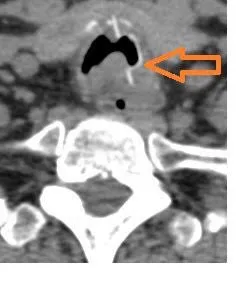

Hình ảnh dị vật ở khí quản (mũi tên vàng) trên CT ngực và gây phù nề và hẹp khí quản không hoàn toàn (mũi tên hồng)

Ho kéo dài do dị vật đường thở ảnh 3 Dị vật nằm dọc khí quản gây biến dạng, phù nề